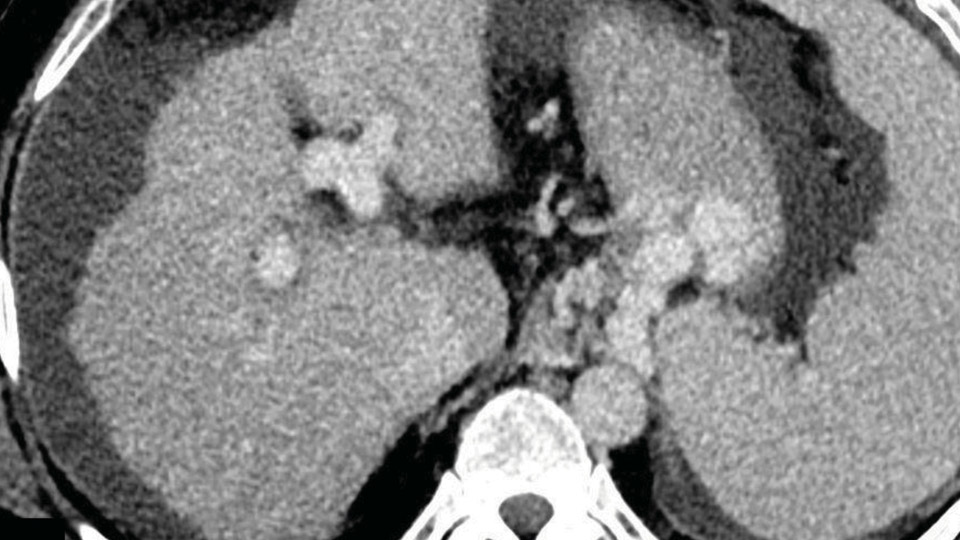

Le foie joue un rôle central dans l’homéostasie et est particulièrement vulnérable aux agressions rencontrées en soins critiques. L’imagerie hépatique, en particulier l’échographie-Doppler et le scanner, est essentielle pour la prise en charge des patients. Cet article explore les principaux aspects de l’imagerie hépatique en soins critiques selon quatre axes. Tout d’abord, des éléments de radioanatomie, de vascularisation et de physiologique du foie sont discutés. Ensuite, les atteintes hépatiques secondaires aux pathologies systémiques, comme les états de choc, l’hépatopathie congestive ou les pathologies infectieuses, sont détaillées. Les pathologies hépatiques intrinsèques, notamment la cirrhose et les tumeurs hépatiques, également fréquentes en soins intensifs sont ensuite abordées. Enfin, la connaissance des grands aspects de l’imagerie post-thérapeutique chirurgicale et endovasculaires fait également de l’approche globale de l’imagerie hépatique en réanimation. L’objectif de cette revue est de donner les clés pour l’interprétation de l’imagerie hépatique de réanimation, abordant d’abord normal et les conditions pathologiques les plus fréquemment observées en soins critiques.